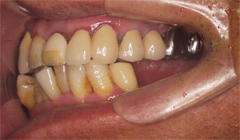

1.インプラント治療(きちんと噛めるように長いインプラントと短いインプラントを組み合わせ治療を行う)

2.マウスピースによる咬合改善維持

3.定期的な予防治療(PMTC)

骨が少なくとも、サイナスリフトという大掛かりな外科手術を行なわずにインプラント治療が実現することができました。